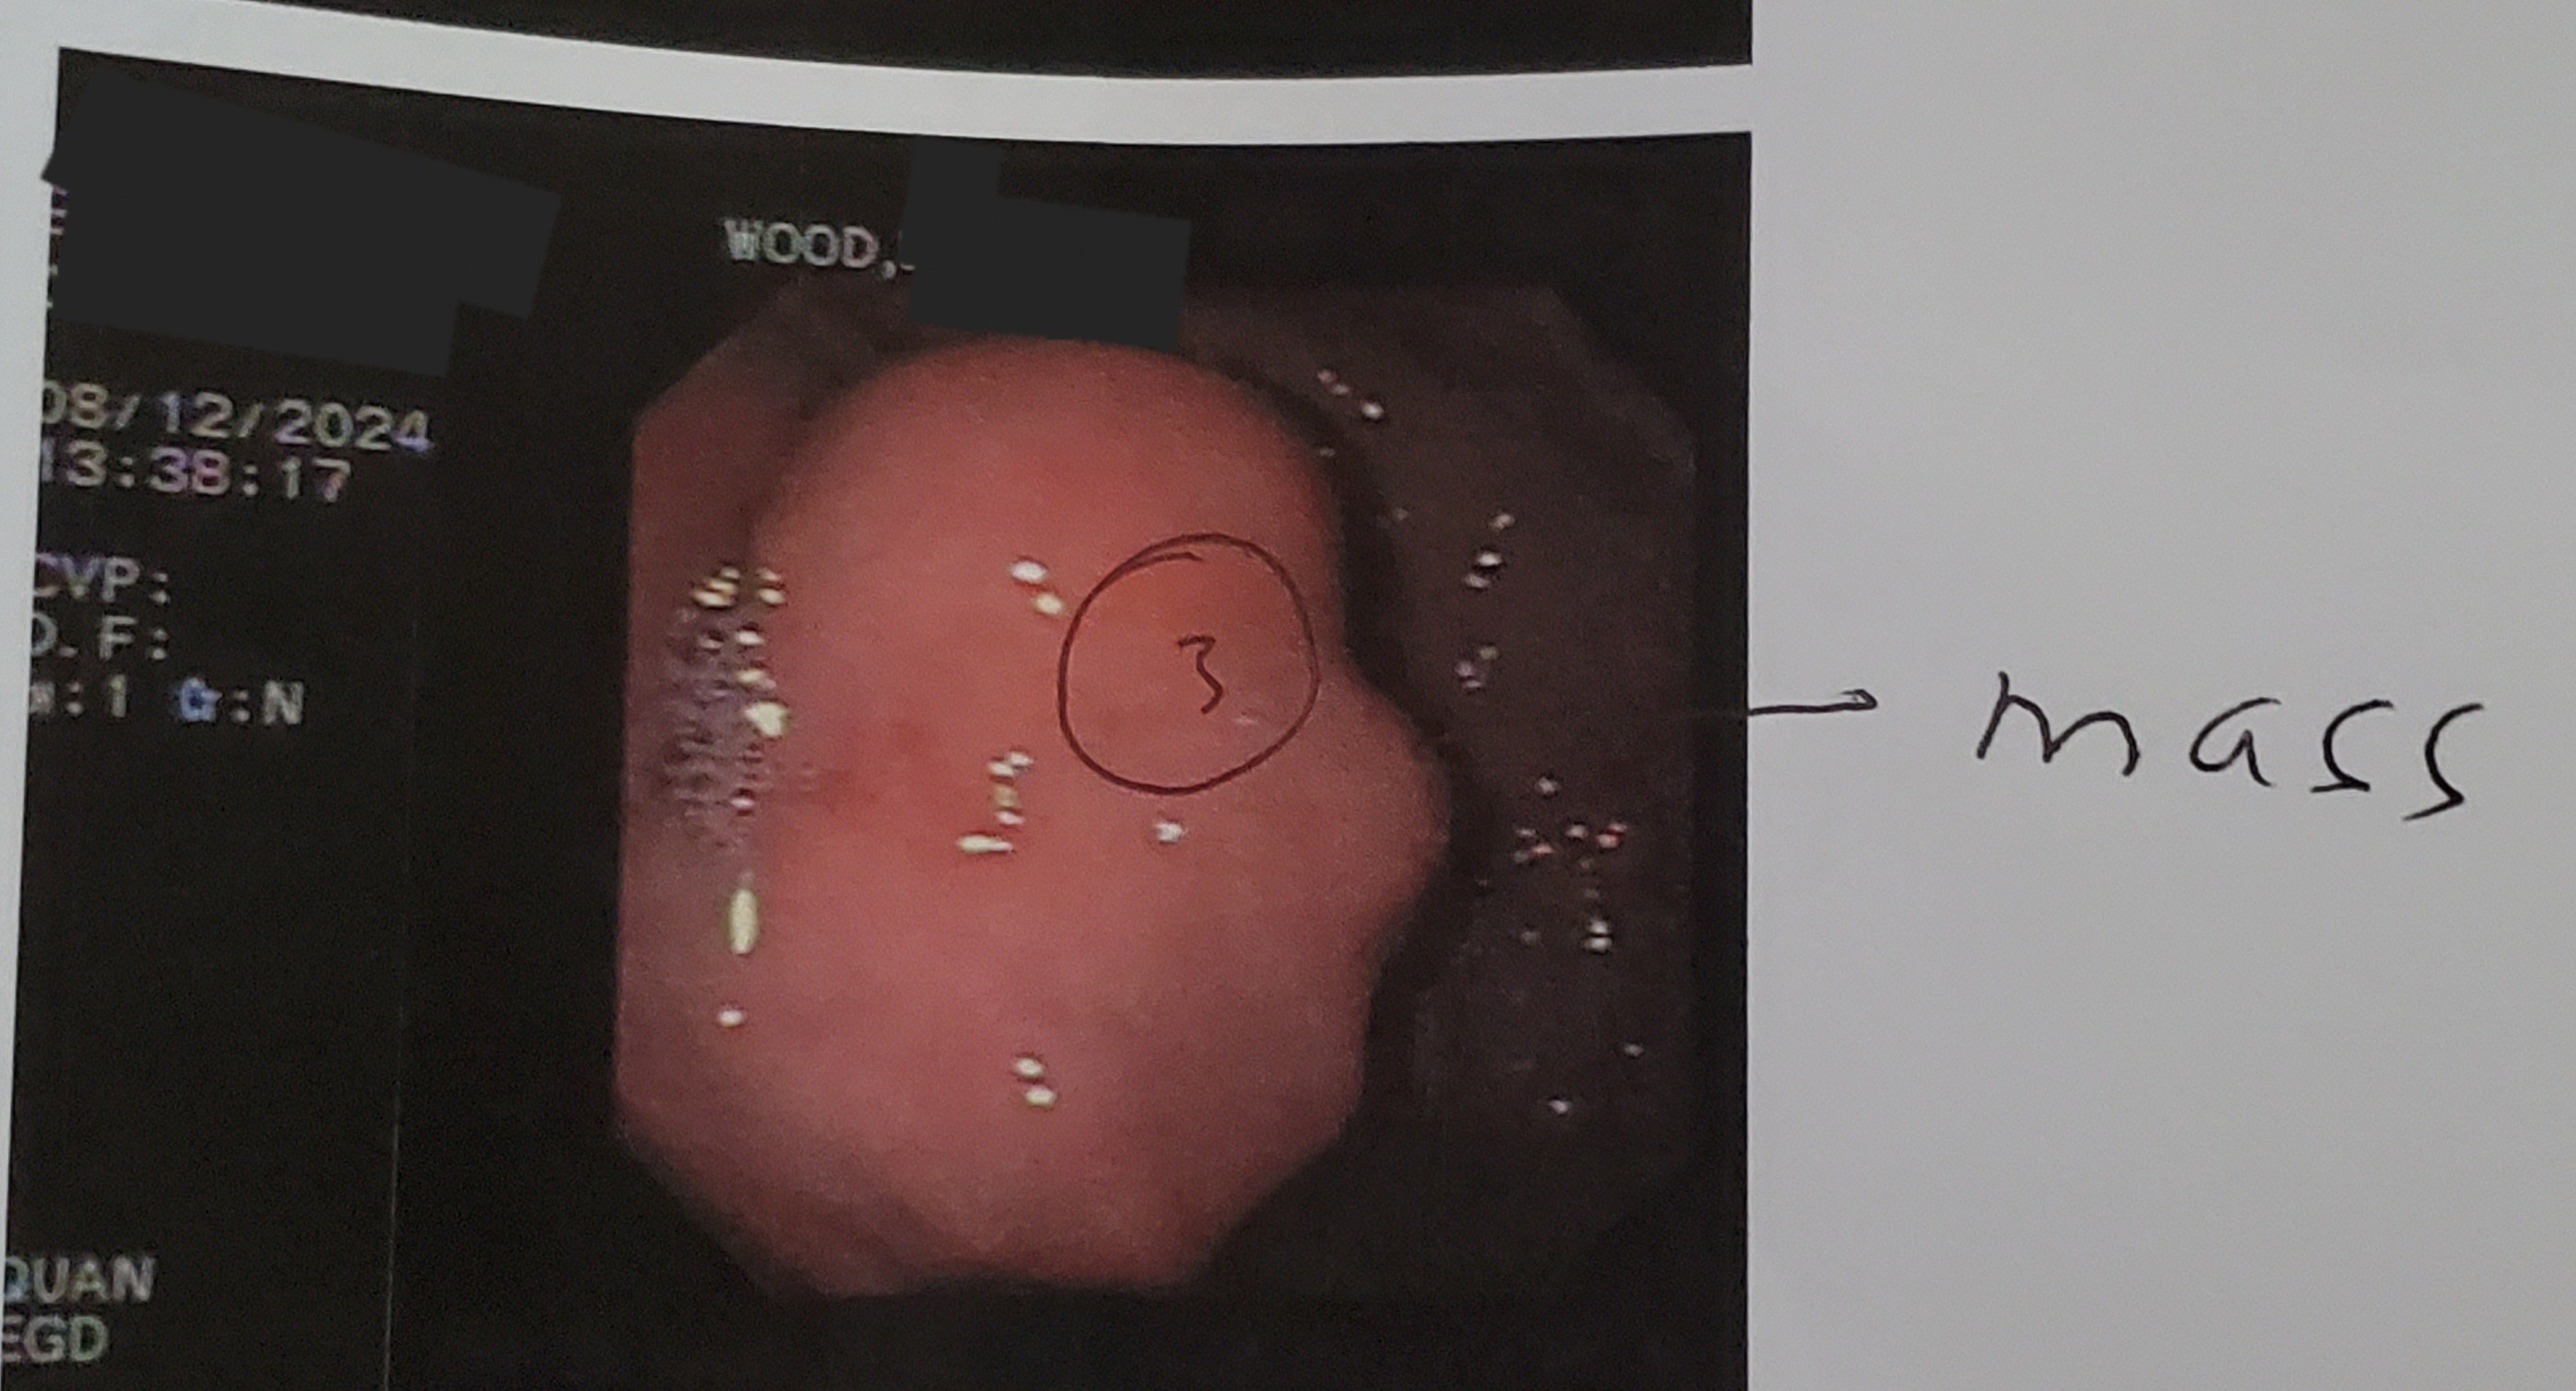

My name is Dedi, and I am facing the most difficult challenge of my life. On July 27, 2024, I was diagnosed with a very rare and aggressive terminal cancer called GIST at Stage 3A. I had the Fundus section of my stomach removed the tumor had busted through my stomach wall and was much larger than what they could see with an endoscopy, x-rays and MRIs. In addition to the GIST, I am also battling right Stage 2 kidney cancer, right Stage 1 lung cancer, and stage 4 of 4 liver failure caused by medications I had to take after multiple knee surgeries and a knee replacements. The physical toll of these illnesses is immense, and I still rely on pain medications just to be able to get out of bed and function each day.